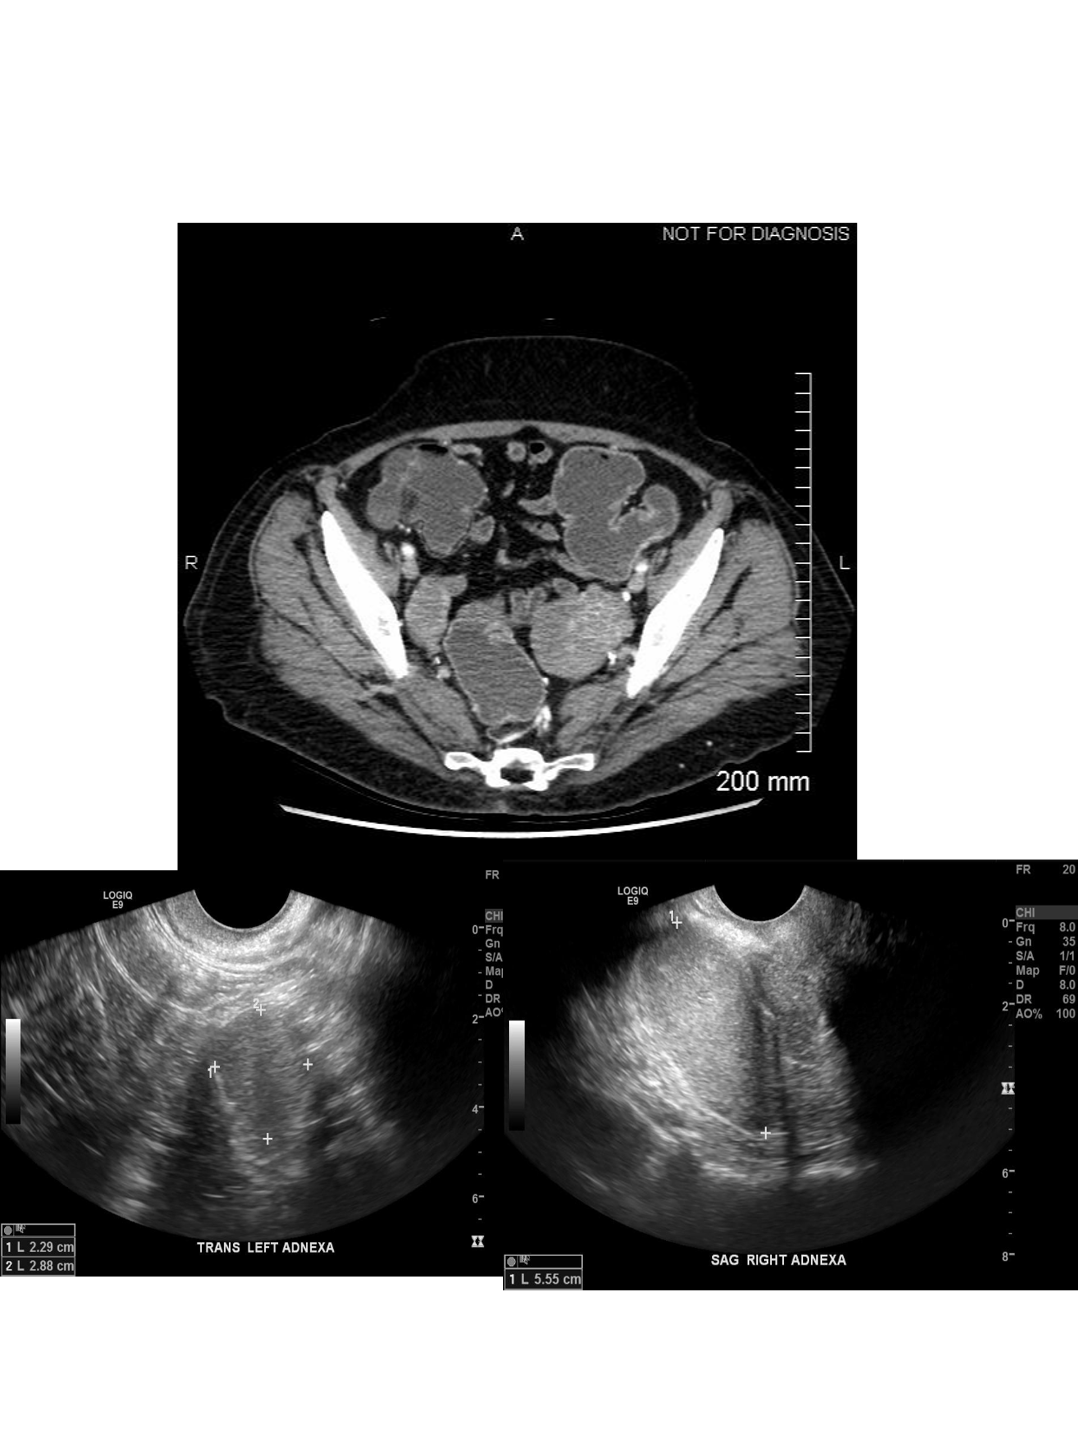

ovarian torsion

The first image demonstrates a normal right ovary. The left ovary is enlarged, midline, does not enhance normally, and demonstrates regions of restricted diffusion, compatible with ovarian torsion. The patient underwent removal of the nonviable left ovary.

most sensitive and specifics signs for ovarian torsion

sensitive sign: enlarged ovary (typically > 25mL)

Specific sign: whirpool sign (twisting of the pedicle)

Additional findings include: